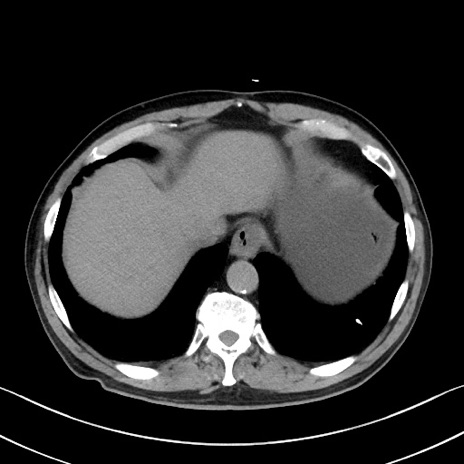

症例35(横断像)

【症例】70歳代 男性

【主訴】腹部膨満、嘔吐

【現病歴】昨日より腹部膨満感出現。本日増悪し、仙痛出現。嘔吐あり、受診。

【既往歴】糖尿病、胆摘後

【身体所見】BP 149/80mmHg、HR 74/min、BT 35.9℃、腹部:膨満、軟、圧痛なし。腸雑音減弱あり。上腹部正中切開瘢痕あり。

【データ】WBC 13500、CRP 1.72